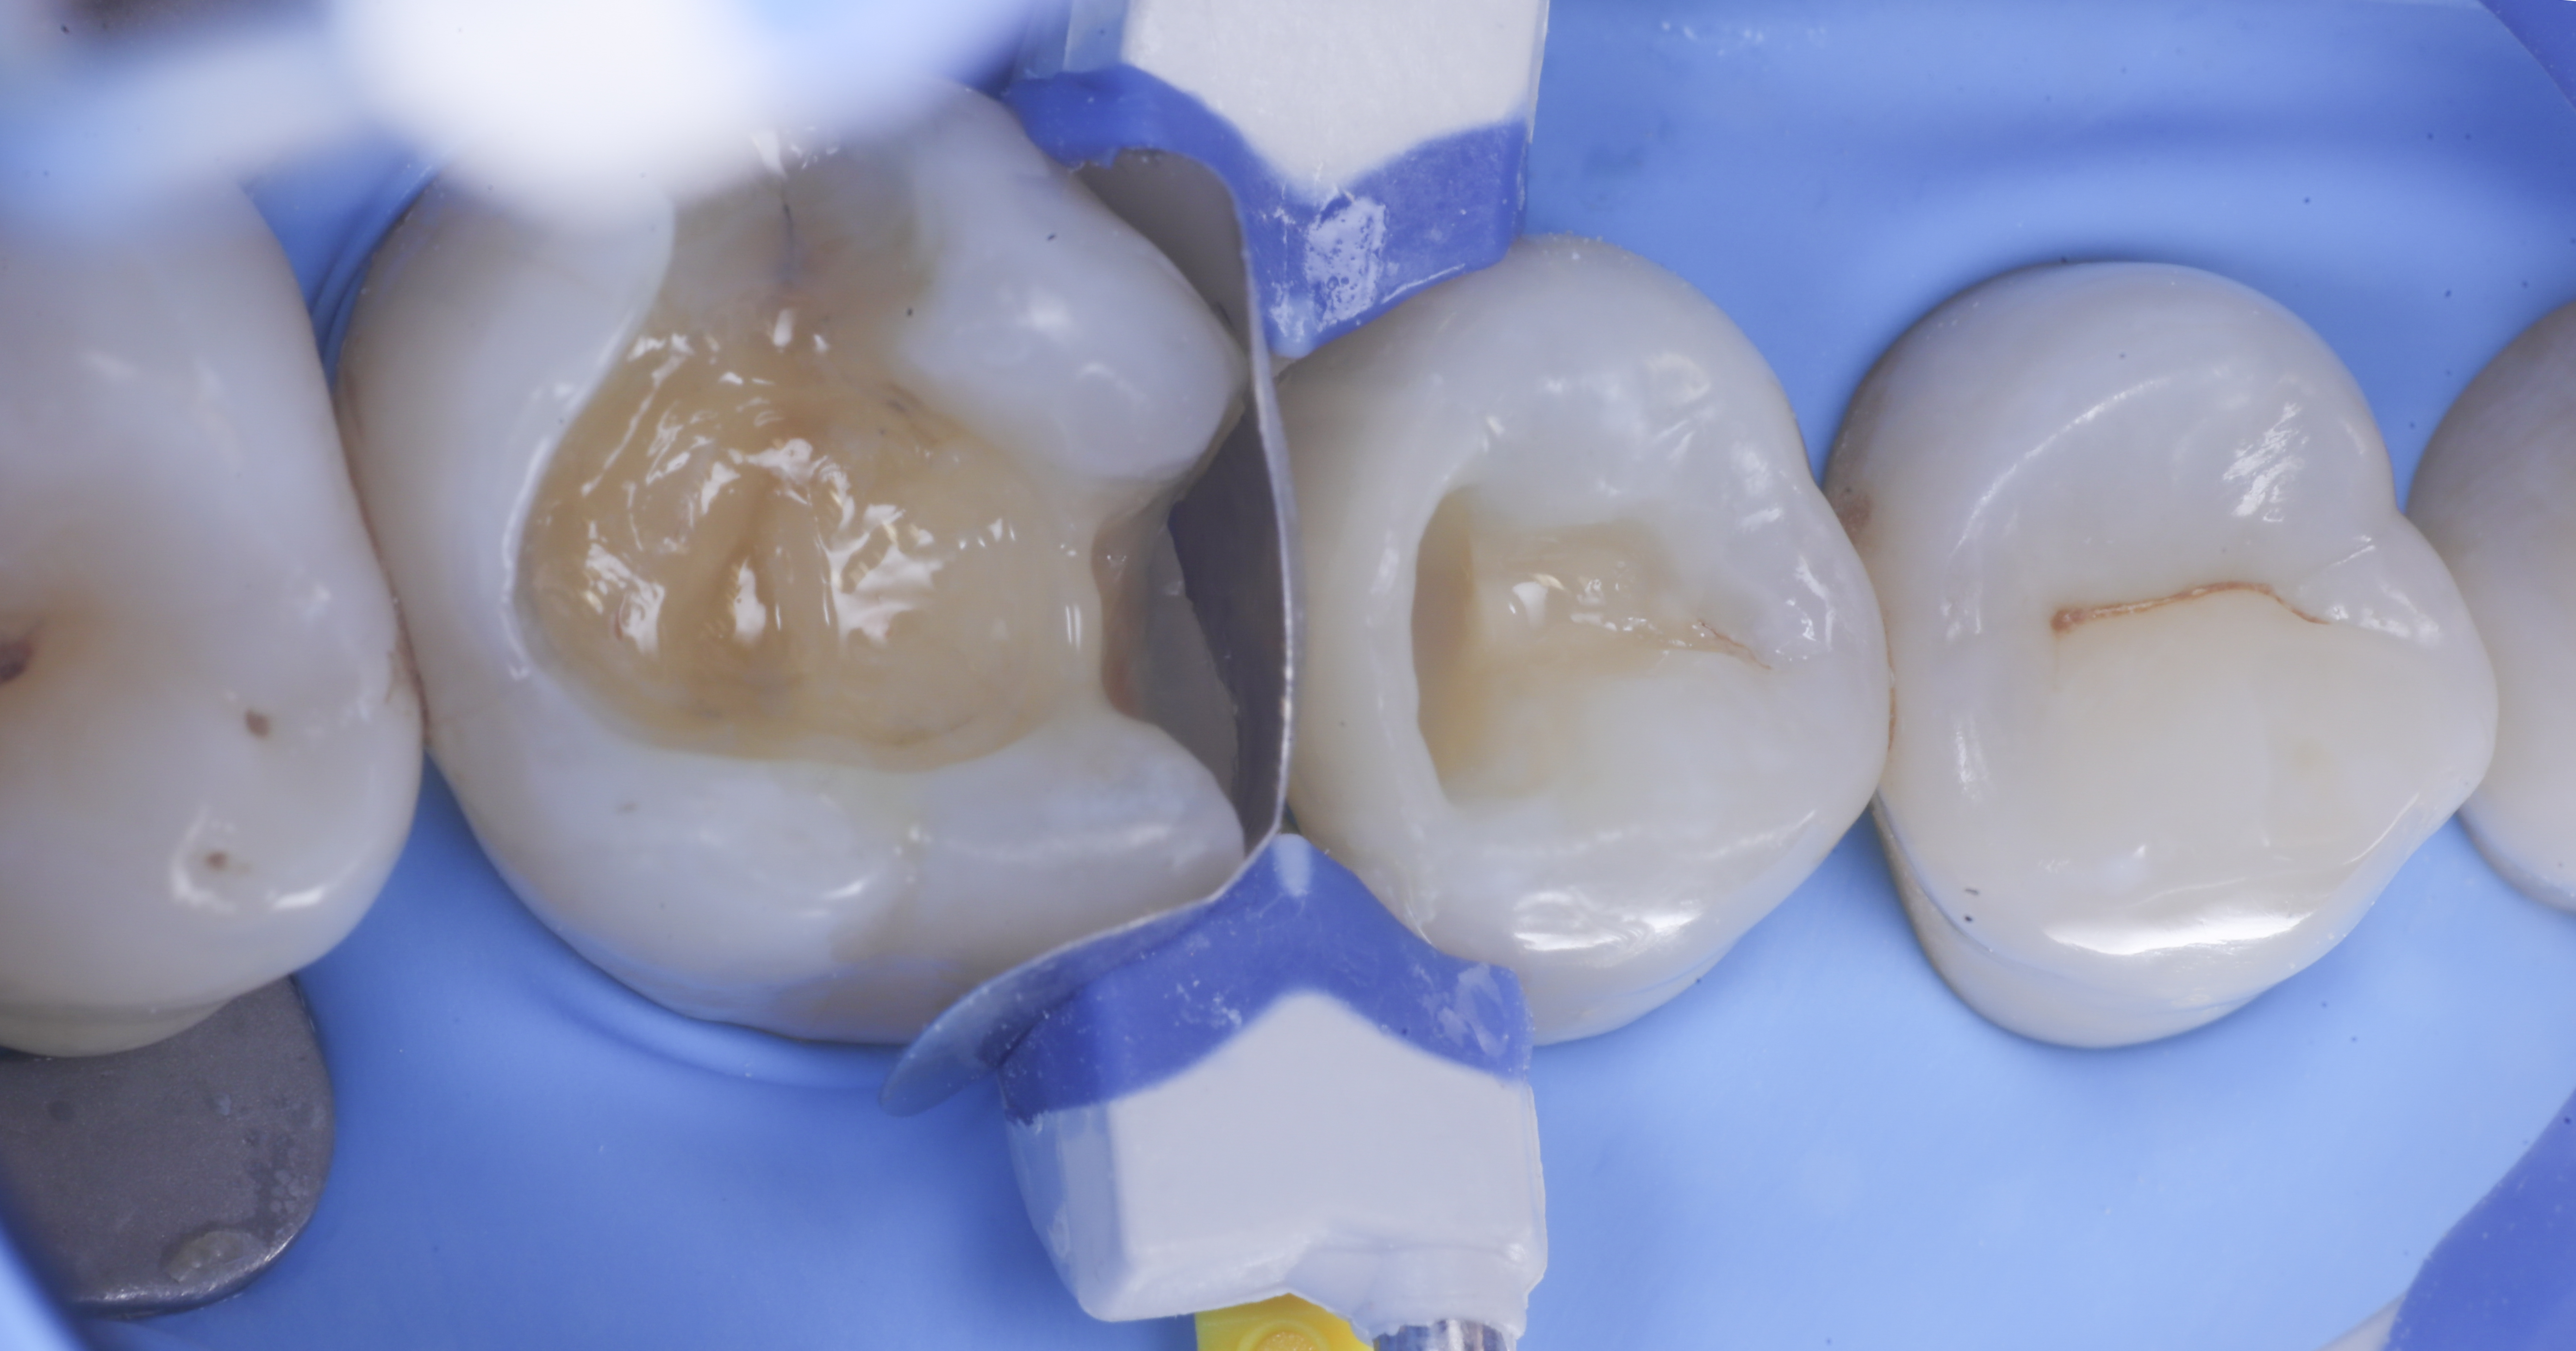

foto 2 Isolamento e aspetto delle cavità ultimate

foto 3 Aspetto vestibolare della cavità ultimate

foto 4 Aspetto della chiusura cervicale e sulle pareti assiali dato dalla prima matrice

foto 5 Aspetto della chiusura cervicale e sulle pareti assiali della seconda matrice